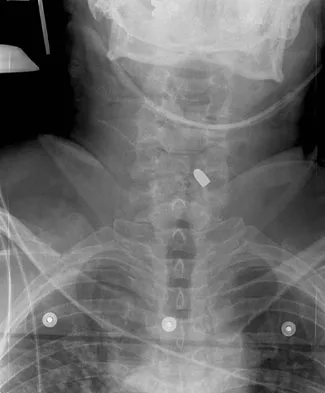

Figures 27a through 27c show the radiographs and CT scan of a 27-year-old man who sustained a low-velocity gunshot wound to the neck. He is quadriplegic (ASIA A), hemodynamically stable, and does not have drainage from his wound. After initial resuscitation and stabilization, the cervical spine and spinal cord injuries are best managed by

Explanation

Although the spinal canal has been penetrated, the lateral masses are intact bilaterally with only partial destruction of the vertebral body and penetration of the lamina on one side, thus the cervical spine is not unstable and surgical stabilization is not indicated. Dural repair is not indicated since there is no external cerebrospinal fluid leakage. Surgical treatment should be based on the need to treat extraspinal pathology only. Bono CM, Heary RF: Gunshot wounds to the spine. Spine J 2004;4:230-240.